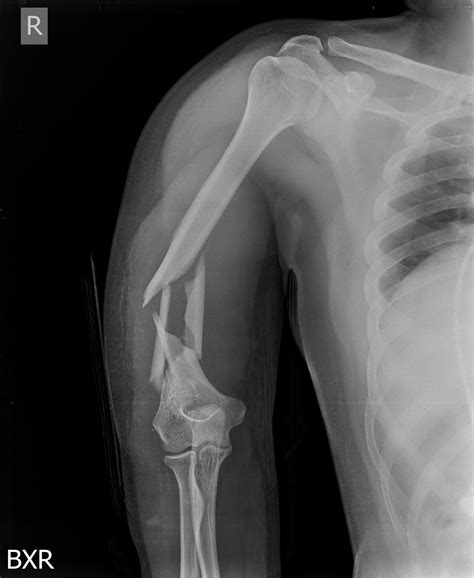

• Deformity: The arm may appear shortened or deformed.

Diagnosis of Humerus Bone Head Fracture

Diagnosing a humerus bone head fracture involves a combination of physical examination and imaging tests. The diagnostic process typically includes:

• Physical Examination: The doctor will assess the shoulder for pain, swelling, and deformity.

• X-Rays: Standard imaging to visualize the fracture and determine its severity.

• CT Scan: For more detailed images, especially if the fracture is complex or involves the joint.